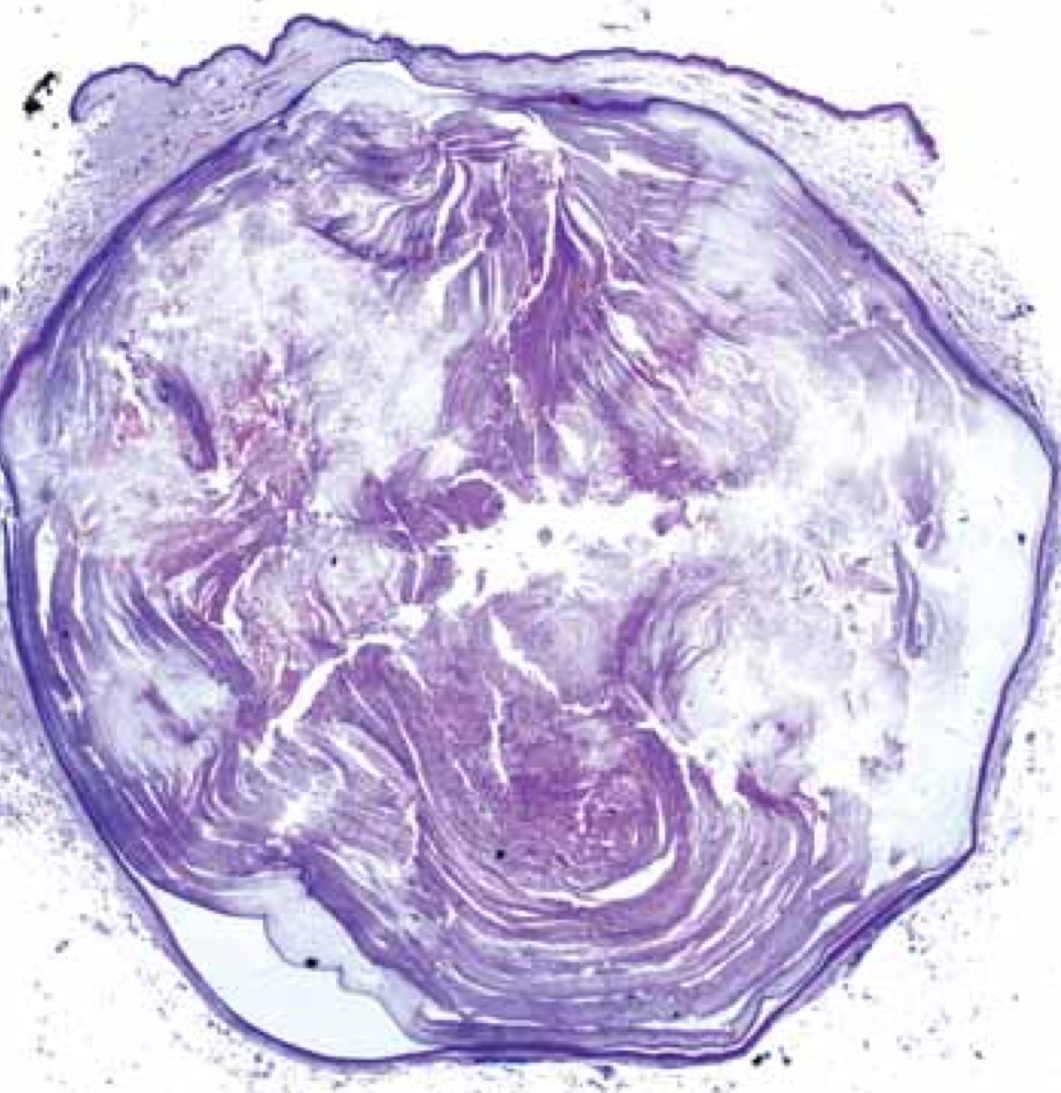

Quiste epidérmico visto al microscopio. Se aprecia fácilmente la cápsula,queratina en su interior y mínimo orificio hacia el exterior.

Extraido de publicación J.L.Rodriguez Peralto, J.Cuevas y R. Carrillo

Imagen histológica de quiste epidérmico.